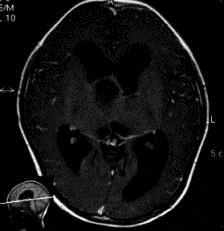

病历摘要:??患者女性,6岁,半年来感觉视力模糊,近10天出现反复头痛,间有恶心呕吐,精神转差,查体:神志清楚,身高90cm,体重25Kg,血压90/55...

问题 病历摘要:??患者女性,6岁,半年来感觉视力模糊,近10天出现反复头痛,间有恶心呕吐,精神转差,查体:神志清楚,身高90cm,体重25Kg,血压90/55mmHg,右眼视力4.6,左眼视力4.8,双侧视乳头水肿,颈软,伸舌居中,四肢肌张力正常,肌力5级,双侧Babinski征(-)。 患者术后第三天,神志逐渐转差,浅昏迷状态,并出现癫痫大发作,体查:颈抵抗,HR110次/分,T38.5℃,BP90/52mmHg,中心静脉压10mmHO,右侧瞳孔2.5mm,光反射迟钝,左侧瞳孔2.0mm,光反射灵敏,刺痛右侧肢体可以定位,左侧肢体见轻微肌肉收缩动作,右侧Babinski征(-),左侧Babinski征(+)。考虑患者病情加重的最可能原因有?

选项 A.高渗性昏迷 B.低渗性昏迷 C.水中毒 D.感染性休克 E.缺血缺氧性脑病 F.脑血管痉挛 G.脑梗塞 H.脑出血 I.无菌性脑膜炎

答案 GH